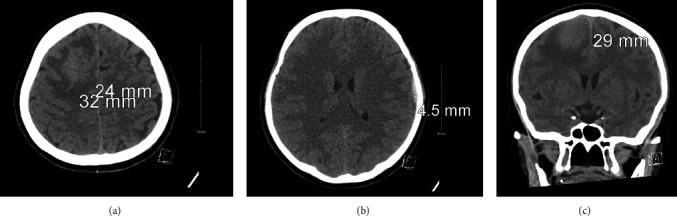

Schistosomiasis is a parasitic infection caused by schistosome invasion of blood circulation. Neuroschistosomiasis is a severe cerebral complication that accounts for less than 2.3% of reported cases. Patients present with progressive encephalitis, seizures, or both. Management includes antiparasitic medications, steroids, and surgical intervention. . We report a case of a 44-year-old female who presented to the ER with a history of transient loss of consciousness (LOC) and seizure. Radiological investigations revealed a right frontal brain lesion. Histopathological results confirmed the diagnosis of schistosomiasis.

血吸虫病是由血吸虫侵入血液循环引起的寄生虫感染。神经血吸虫病是一种严重的脑部并发症,在报告病例中占比不到2.3%。患者表现为进行性脑炎、癫痫发作或两者皆有。治疗包括抗寄生虫药物、类固醇和手术干预。我们报告一例44岁女性病例,该患者因短暂意识丧失(LOC)和癫痫发作史就诊于急诊室。影像学检查发现右侧额叶脑部病变。组织病理学结果确诊为血吸虫病。